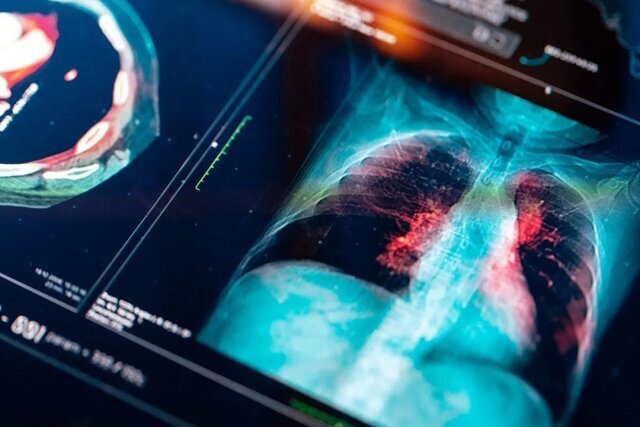

دانشمندان میگویند پروتئینی به نام TLR2 میتواند نشان دهد که آیا بیمار پس از تشخیص سرطان ریه زنده میماند یا قربانی میشود.

به گزارش آیای، بر اساس یک پژوهش جدید که توسط پژوهشگرانی از چندین دانشگاه انجام شده است، سطح پروتئینی به نام TLR2 در تومورها میتواند نشان دهد که آیا بیمار پس از تشخیص سرطان ریه زنده میماند یا خیر.